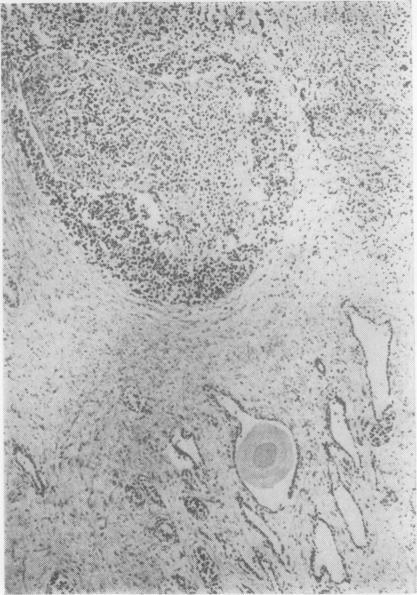

The clinical and pathological findings of a case of systemic angioendotheliomatosis are presented. The previously published cases of this disease are analysed. The present case is only the third to show clear evidence of metastasis.

本文报告了一例系统性血管内皮瘤病的临床及病理表现。对该疾病既往已发表的病例进行了分析。本病例是第三例有明确转移证据的病例。